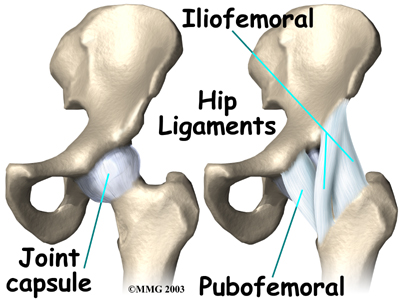

Which parts of the hip joint are affected by a dislocation?

The hip joint is one of the true ball-and-socket joints of the body.

The hip socket is called the acetabulum and forms a deep cup that surrounds the ball of the upper thighbone, called the femoral head. The ball and socket is surrounded by a soft-tissue enclosure called the joint capsule.

The hip itself is surrounded by the thick muscles of the buttock on the back of the hip and the upper thigh muscles on the front.

The joint capsule and ligaments keep the ball joint centered in the hip. When these soft tissues are cut during hip surgery, there is a greater risk for the ball to be forced out of the socket and dislocated after surgery while the soft tissues of the hip heal. The hip precautions you'll learn are used to keep your hip in safe positions. To do this, you need to avoid certain movements and positions. In this way, the ball will be less likely to push against the healing tissues and be forced out of the socket. Most surgeons prefer to have you use these precautions for at least six to twelve weeks after surgery until the healing tissues gain strength.